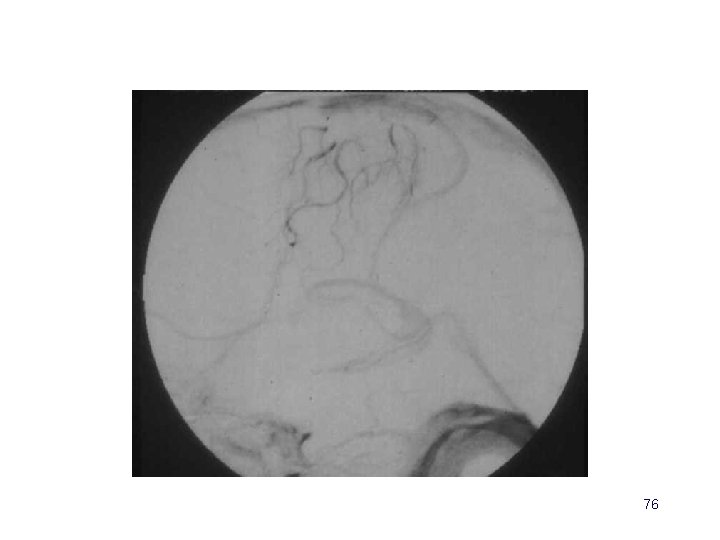

Angiographie • Indications très limitées : – contre-indications et insuffisances de l ’IRM (et de l’angioscanner) • injections globale et sélectives • vues de face, de profil et obliques • temps tardifs 73

Angiographie • Occlusions veineuses (absence d ’opacification) • Retard circulatoire (stagnation) • Circulation de suppléance – veines corticales en « tire-bouchon » – veines trans-cérébrales – veines extra-cérébrales 74

Angiographie • Faux positifs • Flux de lavage (étudier l ’injection globale et les autres axes) • Hypoplasie ou agénésie du sinus latérale (recher la gouttière osseuse, analyser le type d ’arrêt d ’opacification) 75

76